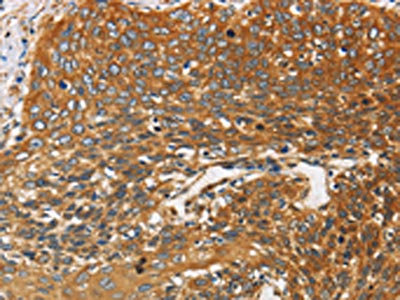

The image on the left is immunohistochemistry of paraffin-embedded Human cervical cancer tissue using CSB-PA176976(DCTN2 Antibody) at dilution 1/25, on the right is treated with fusion protein. (Original magnification: ×200)

The image on the left is immunohistochemistry of paraffin-embedded Human thyroid cancer tissue using CSB-PA176976(DCTN2 Antibody) at dilution 1/25, on the right is treated with fusion protein. (Original magnification: ×200)